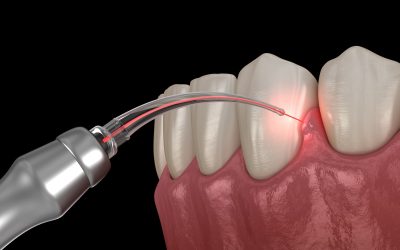

How The Dental Laser Is Breaking The Dental Drill Paradigm

There are two cornerstones to ensuring oral health remains positive throughout your life. The first is maintaining a solid regimen of brushing, flossing, and using mouthwash as part of a dental hygiene routine. The second is ensuring you see your dentist at least...